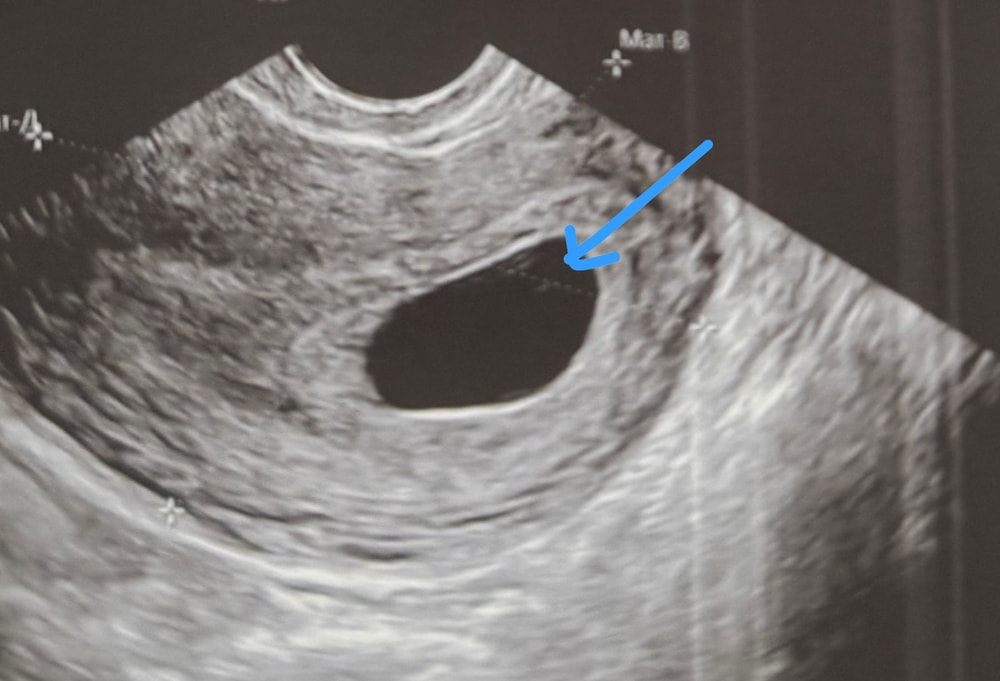

28.06.2025 сегодня была на узи. Плодное яйцо 21,4мм внутри ничего не увидели. Врач сделала заключение анэмбриония. Мне так кажется или в плодном яйце что-то виднеется?